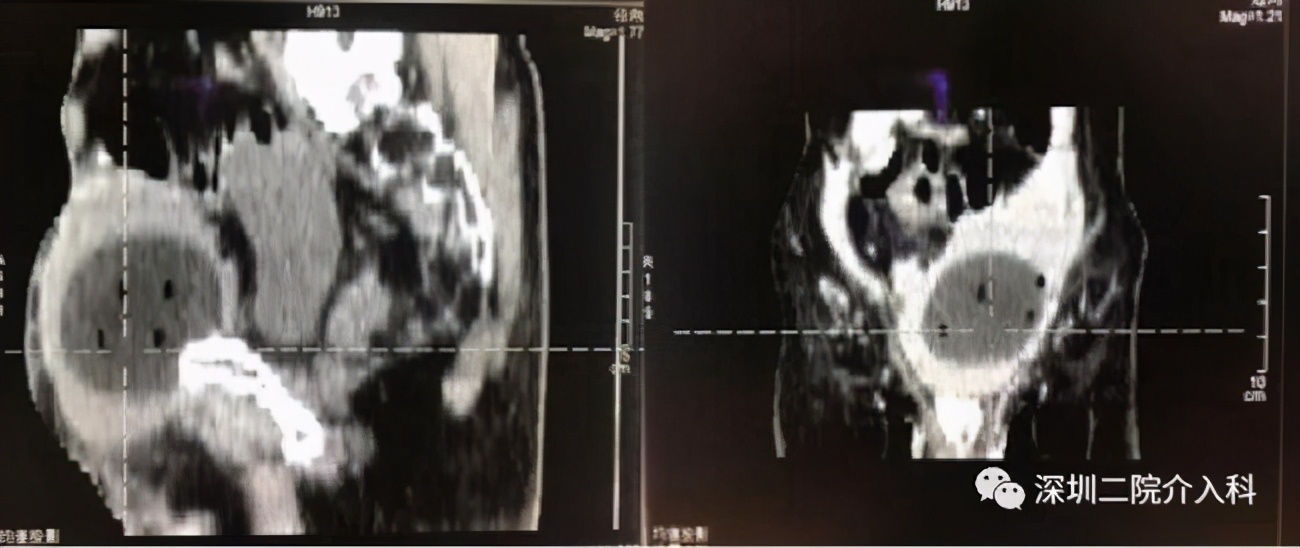

图示CT引导下,经过精密计算肿瘤大小及消融范围后,分别置入4根冷刀: